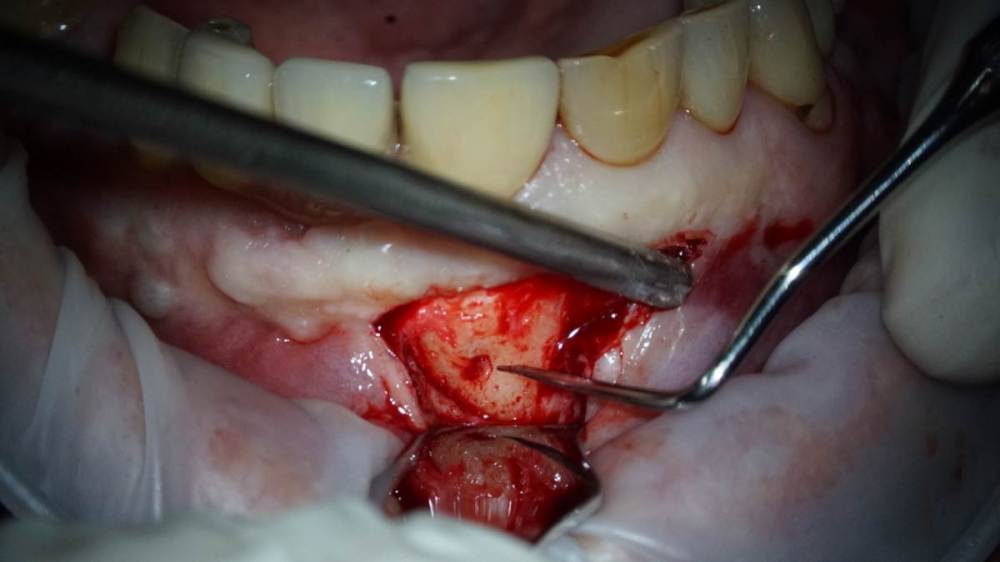

TIGER Опубликовано 1 октября, 2022 Поделиться Опубликовано 1 октября, 2022 Всем хорошего дня!Иногда некачественное эндо может привести к фатальным последствия,тут мы успели принять меры и сохранить и зуб и имплант!Вывод:эндо подготовка зубов прилегающих к зоне имплантации должна проводиться до имплантации!P.s винтик от НКР уже 7 лет там 3 Ссылка на комментарий